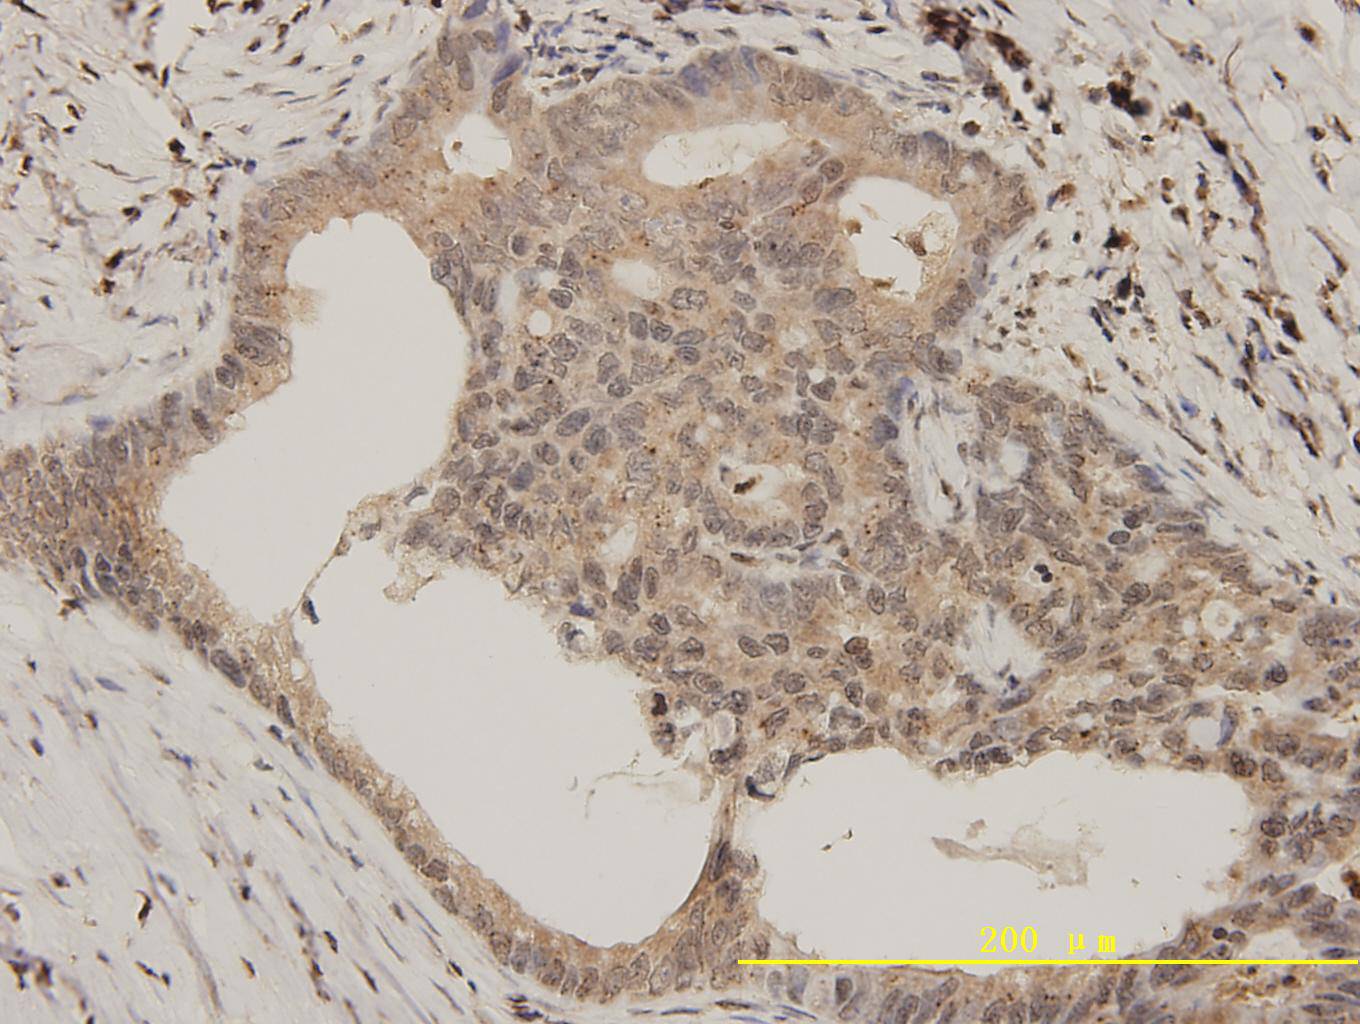

Immunohistochemical analysis of paraffin-embedded human colon carcinoma tissue using anti-Bcl-2 rabbit polyclonal antibody. Counter stained with hematoxylin.